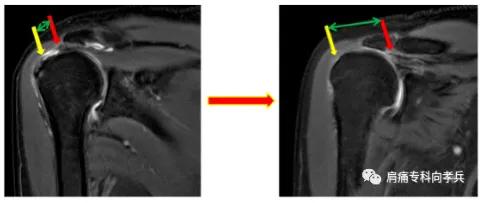

而且需要定期到门诊复查,必要时通过肩关节MR评估肩袖损伤的进展情况,及时调整治疗方案。

经保守治疗效果不佳、肩袖撕裂经MR确认撕裂进展、肩袖损伤较大或对肩关节功能要求较高的患者,建议进行微创治疗,改善肩关节功能。